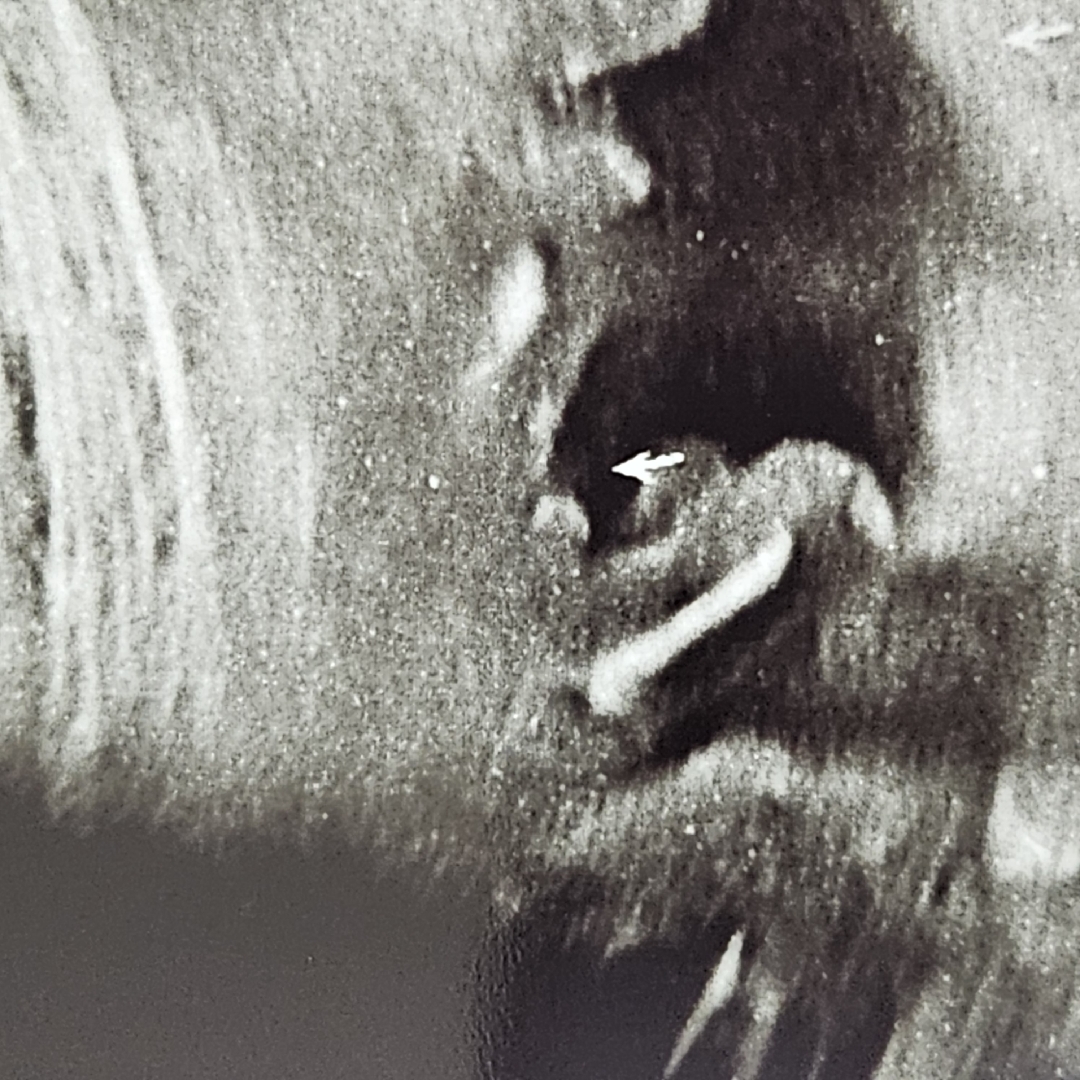

아들일까요!?

왜ㅋㅋㅋㅋ큐ㅠㅠㅠㅠ 삼각형이 아니고ㅠㅠ 동그랗졐ㅋ큐ㅠㅠㅠ.. 우리아덜..

탯줄 같은데요?

탯줄이 동그랗게 찍힌걸까요오!?ㅠㅠㅠ